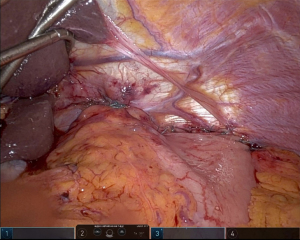

Our paradigm at the University of Pittsburgh has shifted over recent years to consider performing suture gastropexy in place of fundoplication in older and/or frail patients with primarily and/or exclusively obstructive symptoms. Importantly, the principal tenets of formal hernia reduction with high mediastinal mobilization, complete hernia sac reduction, and tension free repair of the hiatus are otherwise identical in all cases, with or without fundoplication (25). If gastropexy is elected in lieu of gastrofundoplication, a series of horizontal mattress sutures are placed along the line of the short gastric vessels to an everted fold of the left diaphragm approximating a line parallel to the anterior aspect of the spleen, thus grossly restoring the physiologic/anatomic position of the gastric fundus to the left upper quadrant (Figure 1). Of note, our technique has evolved to include an initial one to two sutures placed to reshape and reaffix the attenuated angle of His to the left crural pillar, theoretically providing some level of competence to the disrupted gastroesophageal junction/sphincter and disrupted phrenoesophageal apparatus (Figure 2). Overall, the goal is to refashion an intra-abdominal angle of His and restore the relative physiologic position of the stomach within the abdomen.